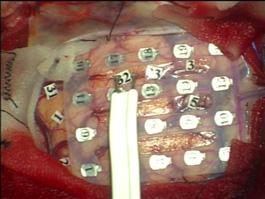

大脳マッピング Brain Mapping

脳の機能を微弱な電気刺激で調べます。運動機能を調べる場合は全身麻酔で手術を行うことが出来ます。

大脳皮質マッピング Cerebral cortex Mapping

大脳の表面の神経細胞の機能を調べます。運動野と呼ばれる体の動きを司る脳を見つけ出し、その部分を損傷しないように注意しながら手術を行います。

皮質下マッピング Subcortical Mapping

大脳皮質の神経細胞の情報は脳内の神経線維を通って脳の他の場所に運ばれたり、脊髄を通って全身の臓器とのやり取りをしています。

脳腫瘍を摘出する際に微弱な電気刺激でこれらの大切な神経線維を確認し、それを傷つけないようにします。当院では独自開発の電極により神経機能マッピングと摘出術を実現しました。

(左図)皮質下マッピング用電極 (NY Tract Finder)

(右図)NY Tract Finderによる神経線維刺激

(図)正確な脳マッピングにより機能を守り腫瘍摘出を行います。